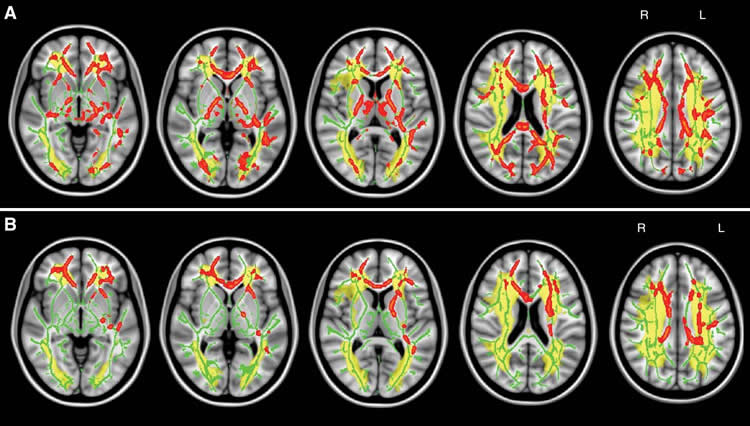

Image shows brain scans of white matter.

FeaturedNeurologyOpen Neuroscience Articles

·September 6, 2016·5 min read

‘Traffic Jam’ in Brain Linked to Common Cognitive Disorder

According to researchers, a simple MRI brain scan could help diagnose people with a common cognitive disorder.

Read More